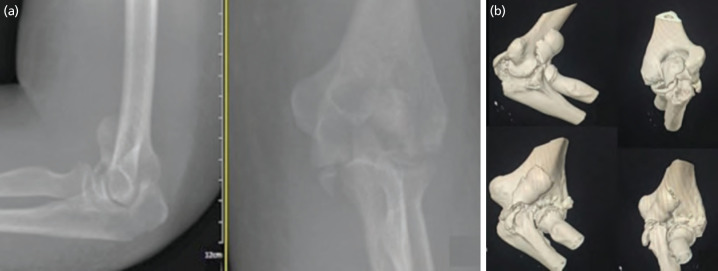

Articular fracture of distal humerus account for 2% of all adult elbow fracture. The coronal shear fracture combined with olecranon fracture require stable anatomical reduction and stabilisation for early rehabilitation and mobility. Numerous reports have described various approaches in tackling this type of fracture and method of fracture fixation. Here, we shared a case of a lady with traumatic coronal shear capitulum and trochlear comminuted fracture fixed using posterior elbow approach with fracture site open window technique in managing distal humerus articular fracture with ipsilateral olecranon fracture using headless screw and tension band wire. During last follow-up, fracture was united radiographically with congruent articular joint, patient able to return to her original function without limitation and no indications of avascular necrosis.